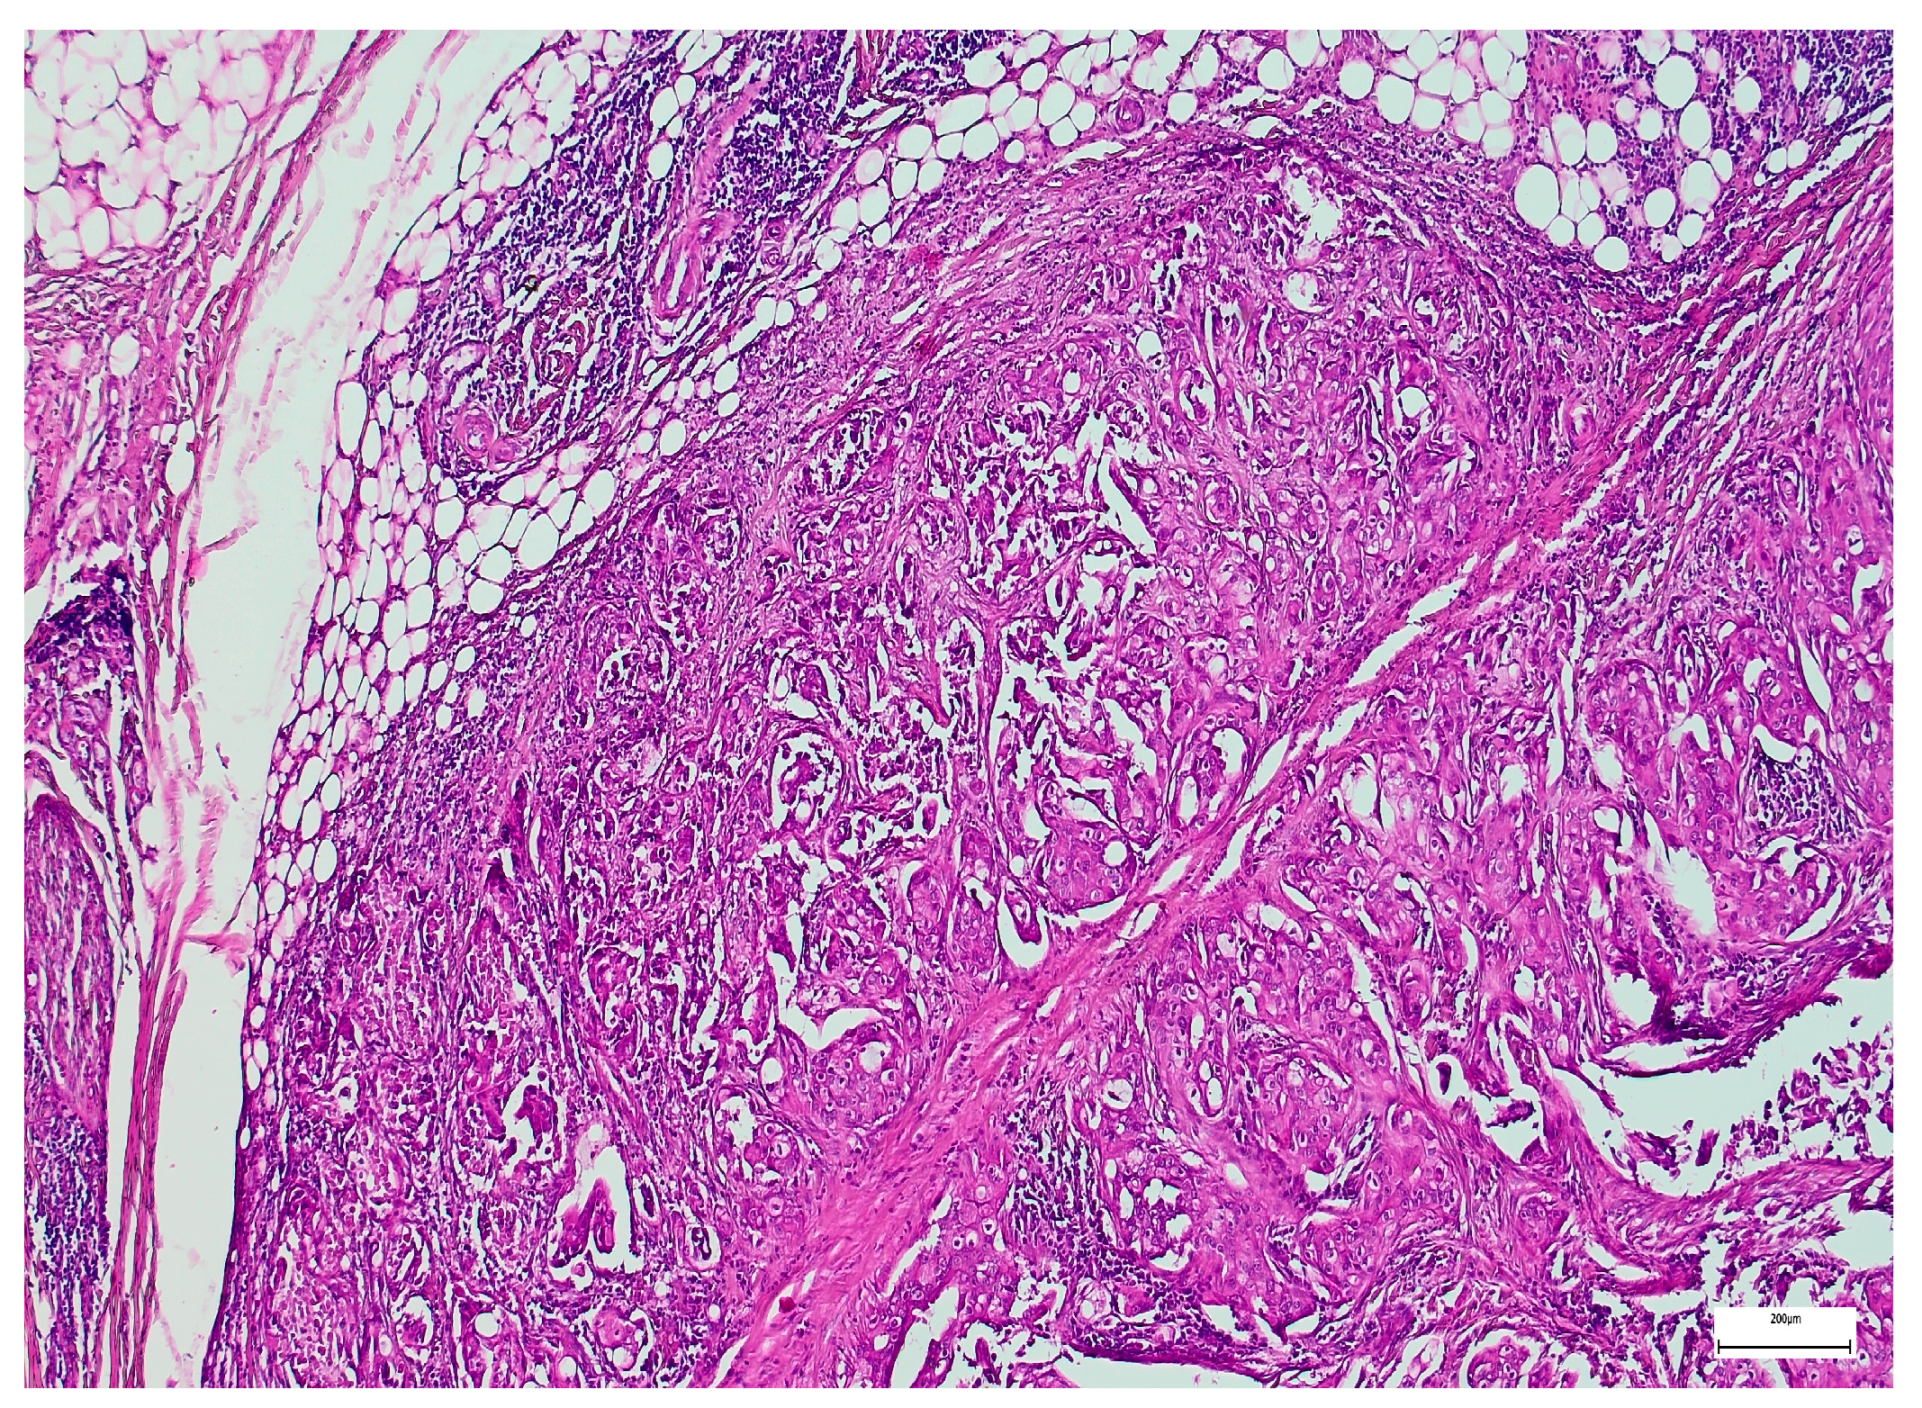

3. Results

3.2. Qualitative and Semi-Quantitative Assessment of SOX-2 and EZH-2 Immunoexpression